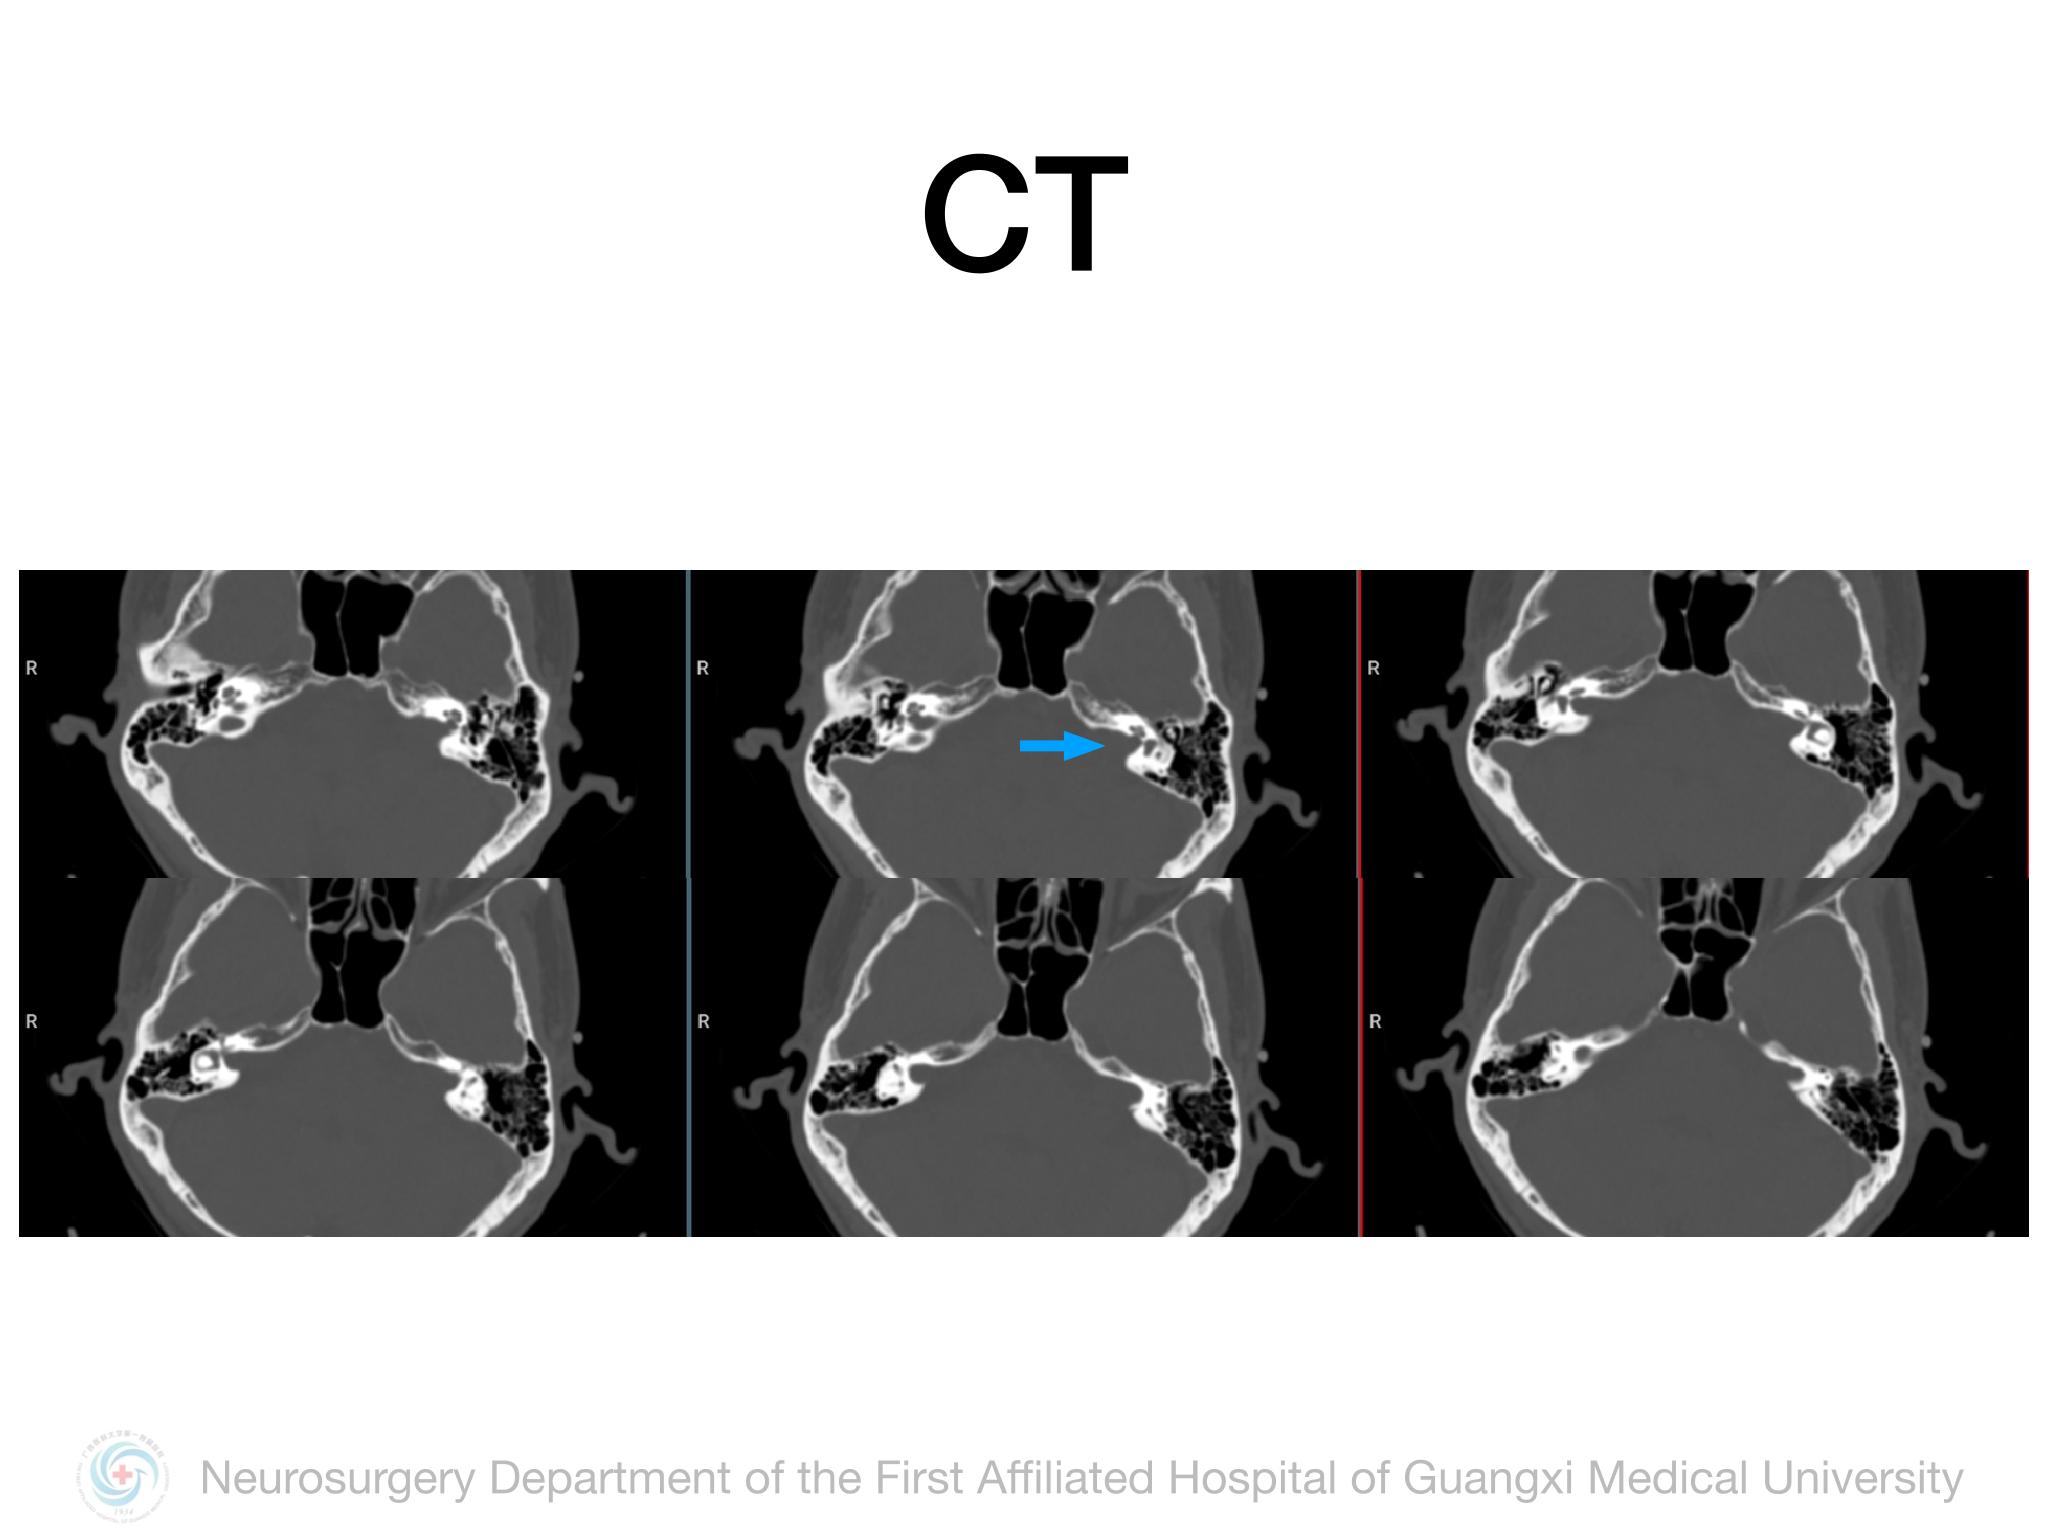

乙状窦后入路切除Koos3级听神经瘤

脑肿瘤-神经鞘瘤